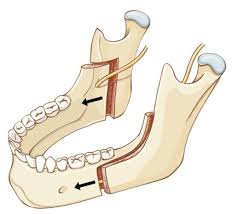

>1) Пластика десны, когда кусок кожи с нёба отрезают и пришивают к десне, чтобы закрыть оголившийся участок

Недавно сделал с двух сторон сверху.

У меня уже сильно оголились + из-за брекетов убыль костной ткани.

Полностью закрыть не удалось, но ткани десны утолщили, потому процесс должен как минимум замедлиться.

За счёт хорошей гигиены кариеса нет.

Кстати сами смотрите свои снимки перед брекетами и, если мало кости, то это хуёвая затея - можно без зубов остаться в итоге.